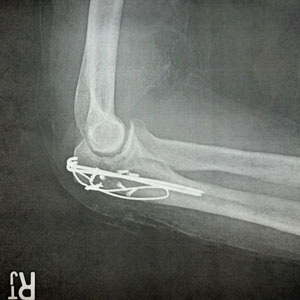

Anderson reportedly fractured his elbow and had cuts and bruises, but seemed relatively positive.